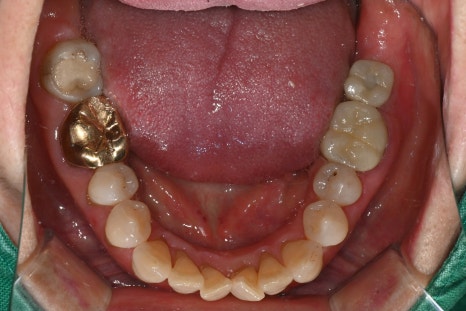

Especially for molars,

left-right balance

distribution of chewing force

occlusal stability

are important,

so an overall design is needed.

Changes after treatment

After treatment, the patient experienced

restoration of molar chewing function

reduced pain

stable occlusion

They also said it felt comfortable when chewing.